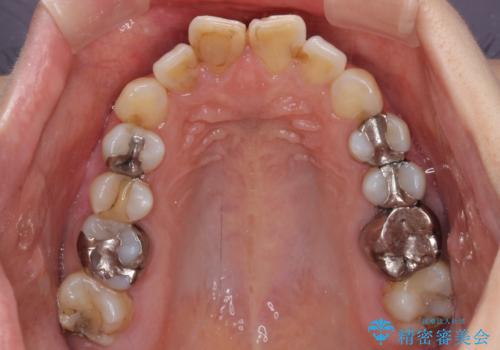

- 前歯のデコボコを治したいとのことで来院された患者様です。

上下顎ともに歯列全体の後方移動とIPR(歯と歯の間を削る)によってデコボコが解消するように設計し、インビザラインにより治療を行うこととしました。

しっかりと装着時間を守ってくださったのですが、途中妊娠にともなう悪阻や出産といったイベントがあり、予定よりも治療期間が長くなりました。